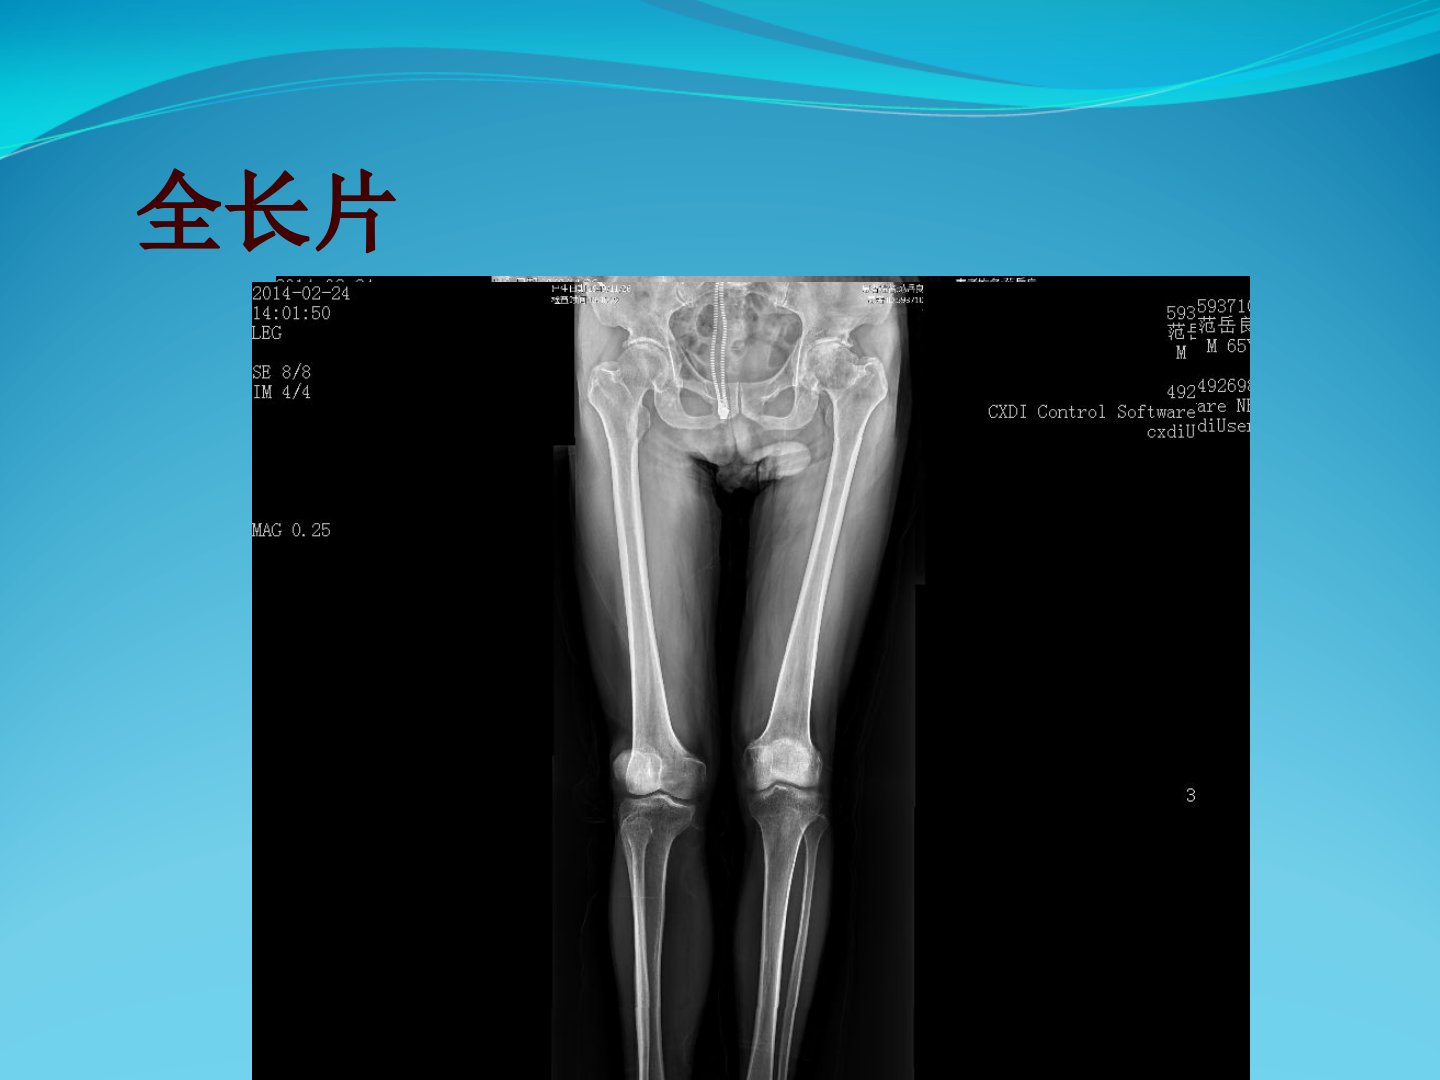

患者为65岁男性因“左髋疼痛15年加重伴活动受限1年余”入院。查体显示左髋存在压痛左侧“4”字征呈阳性左髋活动明显受限尤其以外展受限显著屈曲约135度后伸约25度外展仅10度内收及内外旋功能尚可。患者足背感觉运动正常股四头肌及胫前肌肌力为5级病理征阴性生理反射存在。患者进行了详细的术前检查包括X线片、CT片及三维CT片并进行了术前步态评估及术前准备。手术过程顺利术后复查X线片及CT片显示臼杯前倾和股骨侧前倾均良好并进行了术后步态评估。生产计划部内容与本病例无关。